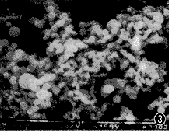

表葡菌敗血症按常規取標本菌株鑑定出葡萄球菌。用新生黴素藥敏紙片,血漿凝固酶試驗等鑑定,血漿凝固酶陰性、新生黴素敏感判為表皮葡萄球菌。採用藥敏試劑盒即:氨苄青黴素、青黴素G、氨苄青黴素/青黴烷碸、苯唑青黴素、紅黴素、氯林可黴素、潔黴素、萬古黴素、氧氟沙星、環丙沙星、頭孢哌酮/青黴烷碸,羥氨苄青黴素/青黴烷碸。

表皮葡萄球菌(staph,epidernidis)是醫院嬰幼兒血液感染的主要病原菌之一,過去從血液中分離出表皮葡萄球菌大多數認為是污染菌,近幾年來報導對人類尤其嬰幼兒的感染有逐年增多的趨勢,從藥效結果可見青黴素耐藥率高達96%,紅黴素;氯林可黴素分別88%、72%,潔黴素也達到52%,頭孢哌酮/青黴烷碸在表皮葡萄球菌敗血症套用效果非常顯著,敏感率達到94%以上。伴隨著抗生素的廣泛套用細菌耐藥性逐漸增加,而且多是耐藥株導致的感染;因此細菌感染必須做藥敏試驗,合理使用抗生素,加強醫院感染的控制,提供依據。